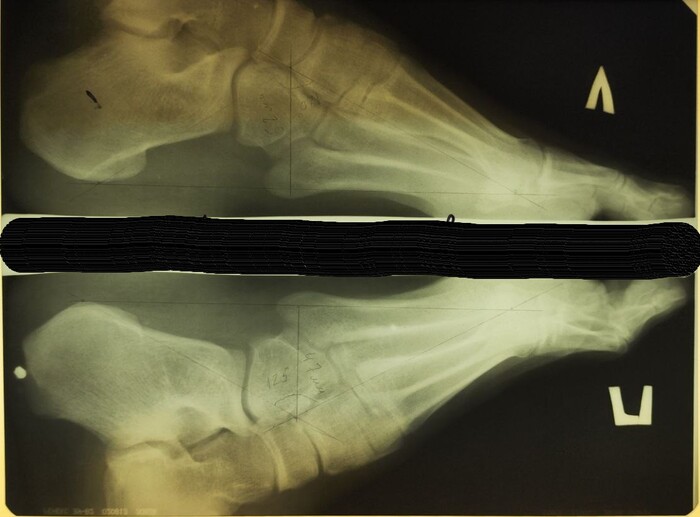

На рентгенограмме костей таза: суставные щели тазобедренных суставов неравномерно сужены, с выраженными краевыми остеофитами в верхне-наружном отделе. Субхондральный склероз суставных поверхностей. Головки бедренных костей уплощены, скошены, структура костной ткани с участками просветления чередующихся с участками остеосклероза. Шейки бедренных костей расширены. Заключение: Двусторонний коксартроз 3 ст. Асептический некроз головок бедренных костей.